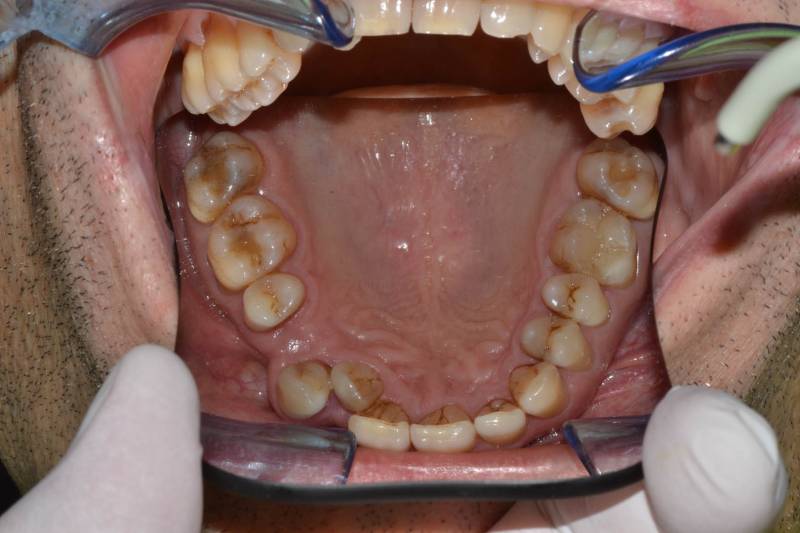

Paziente trattato con ortodonzia fissa bimascellare per 20 mesi.